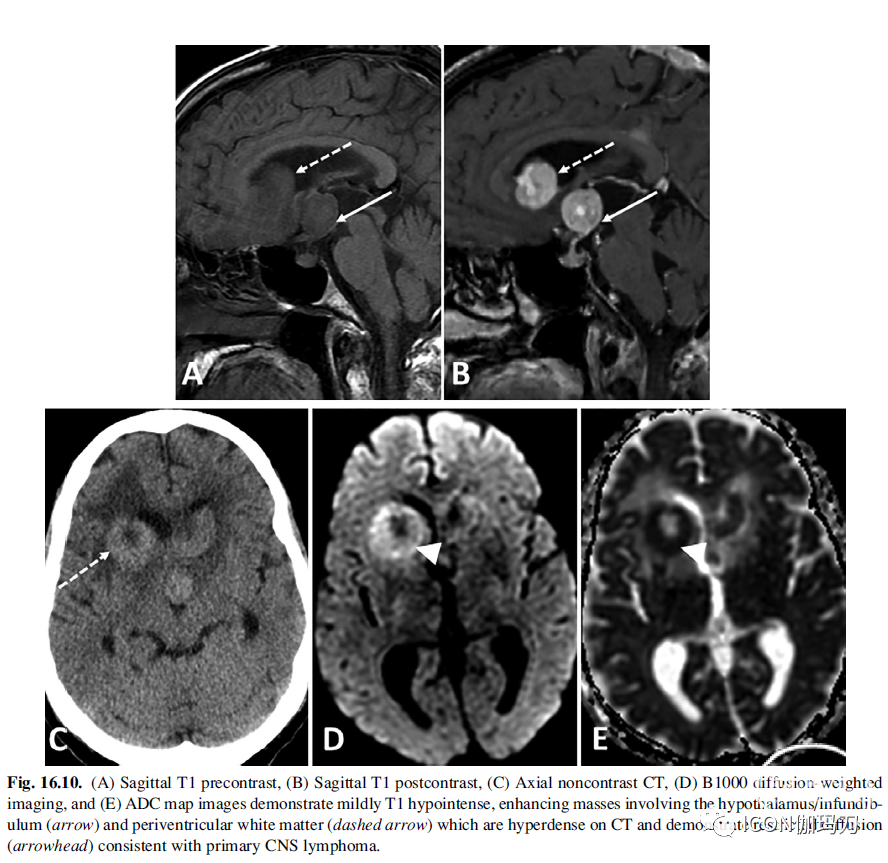

PCNSL是多细胞性的(hypercellular),破坏血脑屏障,并经常接触脑膜表面。平扫CT上肿块通常呈等至高信号,增强成像上强化。在具有免疫力的患者中,肿块在T 1加权成像上呈均匀等/低信号,在T加权序列上信号多变,并表现出强烈的均匀强化(图16.10)。在免疫功能低下的患者中,病变经常表现为出血或坏死,导致T1和T2加权信号特征更不均匀,周围强化。缺乏强化是极其罕见的。漏斗部受累的特征是漏斗部增厚,高强化,同时没有PPBS 。在T2*梯度回波序列上可能出现开花现象。病灶周围水肿,可见肿块周围T2高信号,与其他中枢神经系统肿瘤(包括胶质瘤和转移瘤)相比不明显。PCNSL通常表现为弥散受限,因为其富细胞(hypercellularity),ADC值可能低于胶质瘤和转移瘤。MR灌注成像通常显示相对脑血容量减少,这有助于区分PCNSL与高级别胶质瘤和转移瘤。经常进行脑部活检以确定PCNSL的诊断,疾病的分期包括PET/CT以排除全身受累和全神经轴的MRI。

图16.10.(A)矢状位T1平扫,(B)矢状位T1增强,(C)轴位平扫CT, (D) B1000弥散加权成像,(E) ADC图显示轻度T1低信号,强化肿块累及下丘脑/漏斗部(箭头)和脑室周围白质(虚线箭头),CT上呈高密度,弥散受限(箭头),符合中枢神经系统原发性淋巴瘤。